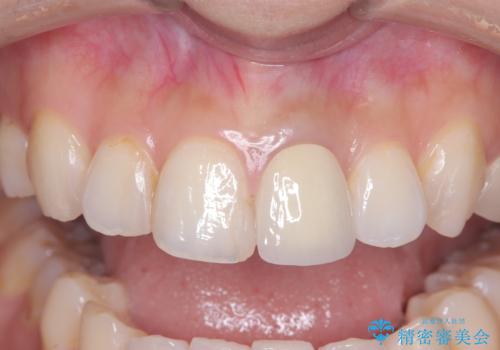

オールセラミッククラウンで治療を行い見た目の改善を行いました。

- 15万4千円(オールセラミッククランスペシャル14万3千円+仮歯1万1千円)費用は治療当時の料金となります

色味は左上2に合わせたいとのご希望だったので、左上2に合わせています。